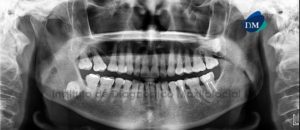

124 – Lesion Endo-Periodontal

Paciente masculino, 71 años de edad, es referido al Instituto de Diagnóstico Maxilofacial – IDM para evaluación de pieza dentaria 13 por presentar dolor y

122 – Sindesmo Corono-Radicular

Paciente femenino de 38 años de edad, procedente de República Dominicana, es referida para su evaluación y diagnóstico. A la evaluación de la radiografía Panorámica

121 – Conducto medio mesial obturado

Paciente masculino, 49 años de edad, es referido al Instituto de Diagnóstico Maxilofacial – IDM (Sede Miraflores) para evaluación tomográfica por presentar molestia a nivel

117 – Canalis Sinuosus

Paciente masculino de 22 años de edad es referido al Instituto de Diagnóstico Maxilofacial (IDM) para su evaluación y diagnóstico. A la evaluación de la

114 – Foramen mentoniano doble

Paciente femenino de 46 años de edad que es referida para la evaluación previa a la colocación de implantes dentales. En la radiografía panorámica se

113 – Osteomielitis crónica

Paciente femenino de 57 años de edad, es referido al Instituto de Diagnóstico Maxilofacial (IDM) por evaluación para la planificación de implantes dentales en zona

111 – Fractura Dento-Alveolar

Paciente femenino, 51 años de edad, es referido al Instituto de Diagnóstico Maxilofacial (IDM) para evaluación tomográfica de las piezas anterosuperiores por traumatismo. En la